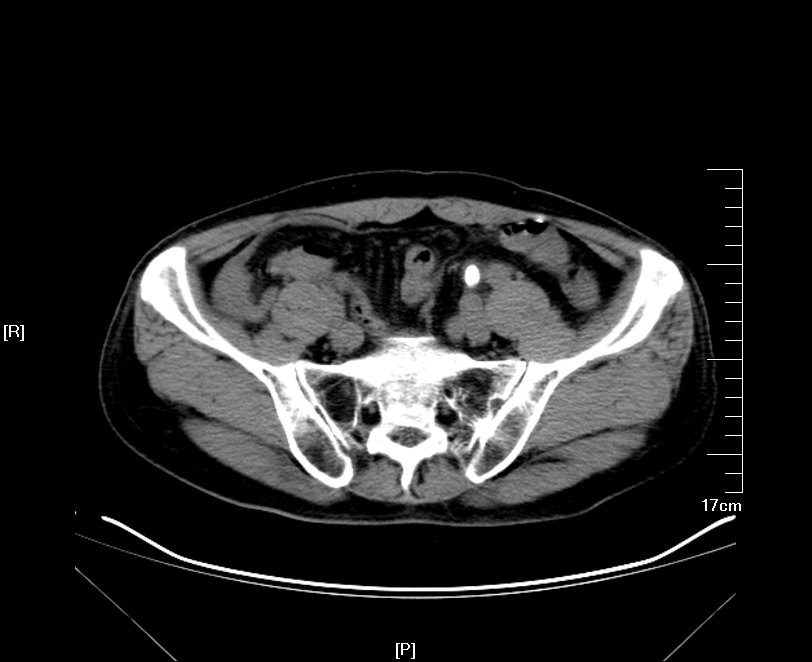

2016年02月手术患者,男性,47岁,河北人,农民,主诉双侧腰部酸胀一年余,伴尿少三天;五年前曾因输尿管结石在当地予以震波碎石3次,后疼痛缓解后未重视,五年来未予以复查,三天前出现尿少,腰部酸胀加重与当地医院就诊后发现病情危重遂来我院求诊,CT:双侧肾脏重度积水,皮质菲薄,双侧输尿管上段扩张明显,双侧输尿管中段结石,左侧结石约1.7cm,右侧约2.8cm左右,GFR:左侧11.7ml/min,右侧16.1ml/min。肾功能:Cr 516umol/L;术前诊断:双侧输尿管结石 双肾重度积水 肾功能失代偿;行双侧经皮肾穿刺造瘘术,保护肾功能,十天后Cr下降至236umol/L,方行双侧输尿管镜检,但由于输尿管梗阻时间太长,输尿管迂曲扩张明显,中段输尿管与周围脏器严重黏连,输尿管镜无法顺利上行,遂行双侧输尿管切开取石术+双侧输尿管裁剪成型术。

CT检查提示:双侧肾脏重度积水双侧输尿管中段结石 双侧输尿管上段积水扩张